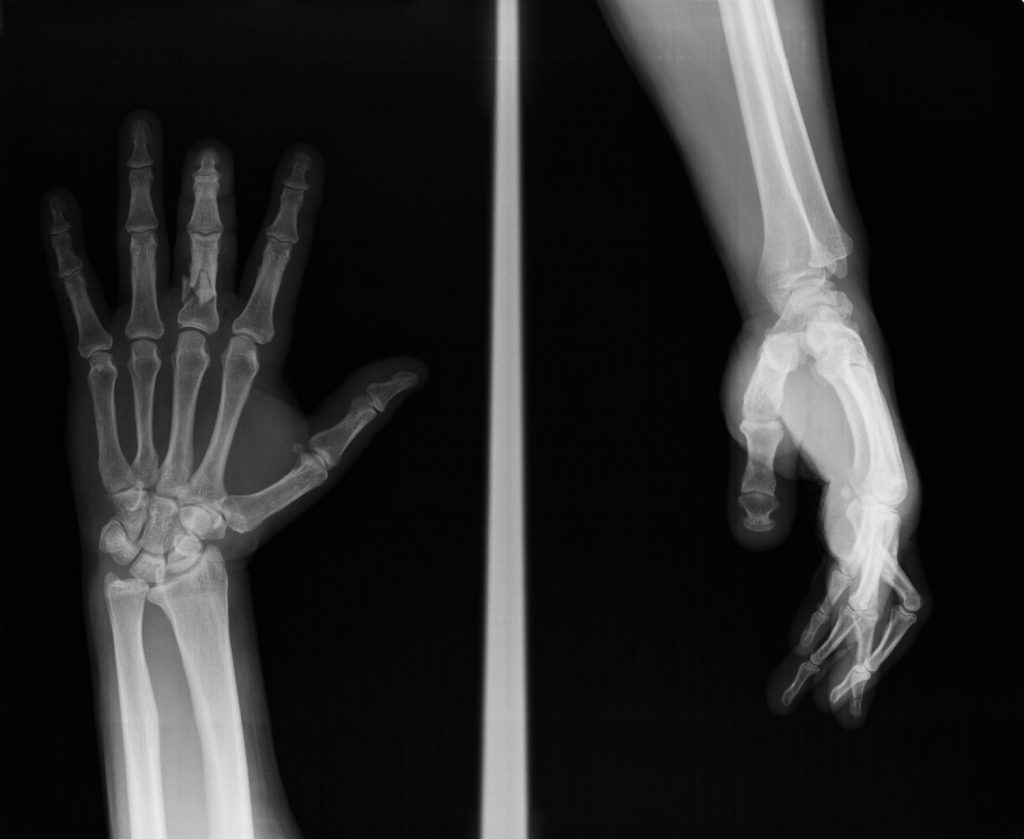

Las fracturas en la mano son relativamente frecuentes. Una fractura puede causar dolor, rigidez y pérdida de movilidad. Algunas fracturas causan una deformidad evidente, (se nota el dedo torcido o rotado – Figura 4), pero otras muchas, no. Por la estrecha relación que existe en la mano entre los huesos, los ligamentos y los tendones, la mano puede quedar rígida y débil cuando la fractura consolida. Las fracturas que afectan a las superficies de las articulaciones (intra-articulares) pueden provocar artrosis precoz en las articulaciones afectadas.

Figura 4 - Deformidad en rotación del 4º dedo por fractura.

Por lo general, para diagnosticar una fractura se necesita una exploración física y radiografías. El Dr. Polo le puede recomendar el mejor tratamiento, dentro de las diferentes opciones existentes según el tipo de fractura.